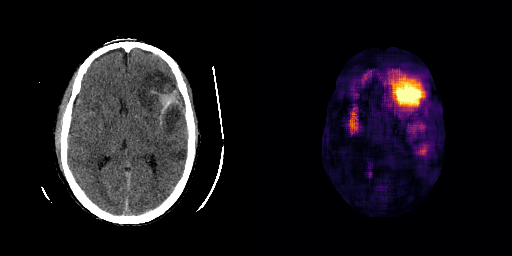

fig:qualitative_ich

ICH

healthy

We show some slices with examples of ICH in \figurereffig:qualitative_ich as well as surface renderings of scans of subjects with cranial fractures in \figurereffig:qualitative_fractures. (As a reference we also included the same examples for the AE in Appendix D in \figurereffig:qualitative_ich_ae.) It is noticeable that the reconstruction error is high where there is an anomaly. The reconstruction error generally seems to continuously depend on the amount of the patch that is anomalous, as the error maps generally seem to be rather smooth.

The performance for the models used for \figurereffig:qualitative_ich and LABEL:fig:qualitative_fractures are shown in \figurereffig:roc_performance. We observe see that the detection of fractures is the more challenging task for our method than the detection of ICH. This might be due to the smaller number of scans available to evaluate it on (see Appendix B). To put these results in context we provided a table with the inter rater agreement on these tasks in Appendix B: The performance in terms of AUROC is around lower than the average raters.